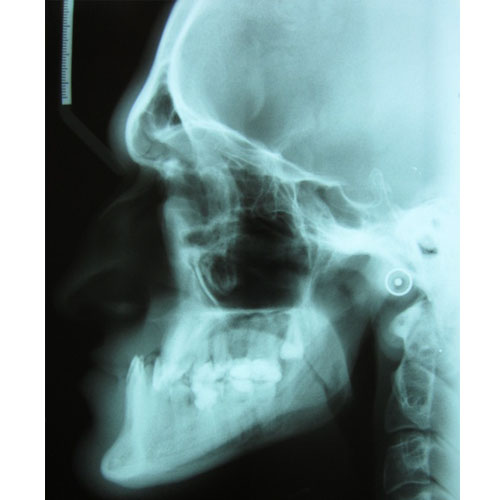

tj. korygowanie nieprawidłowego ustawienia zębów i szczęk. Zęby, które są niefizjologicznie ustawione są trudniejsze do prawidłowego czyszczenia, a tym samym bardziej narażone na próchnicę. Skrzywione zęby powodują ponadto dodatkowe obciążenia, m.in. mięśni żwaczy, a to może być przyczyną bólów głowy, zespołu Costena (zespół bolesnego stawu skroniowo-żuchwowego), mogą się pojawić również bóle szyi czy barków, a nawet pleców. Nieprawidłowy zgryz powoduje również dyskomfort natury estetycznej, co może prowadzić do zakłopotania, braku pewności siebie, a nawet depresji.

Leczenie ortodontyczne może być rozpoczęte w każdym wieku. Niektóre wady wymagają jednak leczenia kompleksowego, wielospecjalistycznego. Skojarzone leczenie dotyczy wad ortognatycznych, czyli wynikających z nieproporcjonalnej budowy szkieletu. Przykładem takiego leczenia jest leczenie progenii.